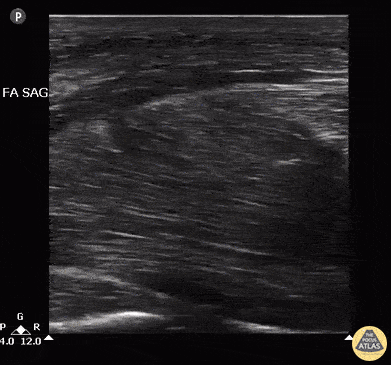

Male with LUE swelling after attempted IV drug use. Ultrasound of bicep reveals intramuscular abscess created from missed injection. Abscess was drained, and pt was admitted and given IV Abx. Image courtesy of Robert Jones DO, FACEP @RJonesSonoEM Director, Emergency Ultrasound; MetroHealth Medical Center; Professor, Case Western Reserve Medical School, Cleveland, OH View his original post here